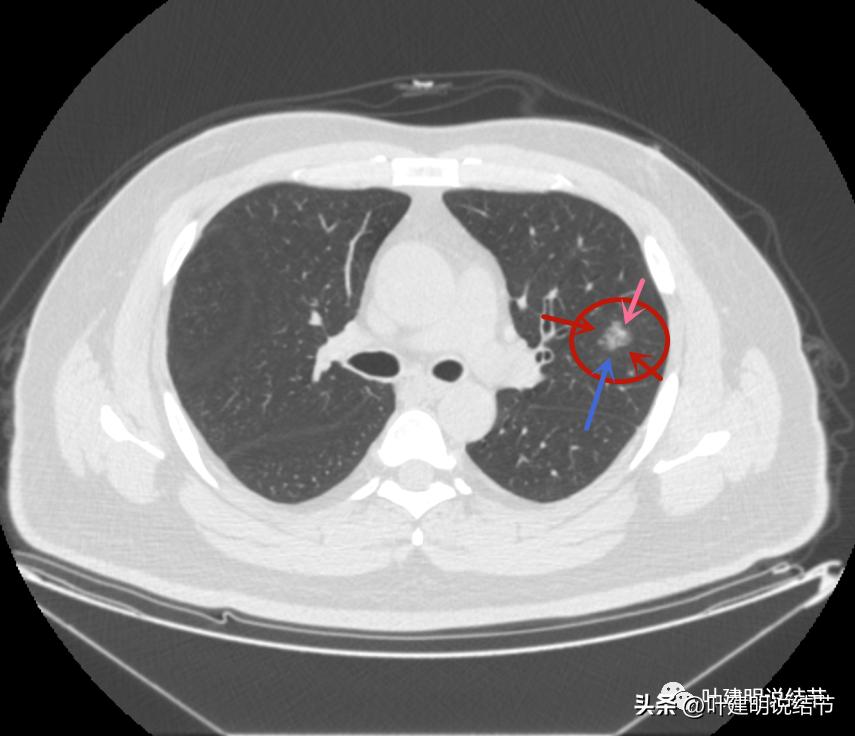

左上病灶4:

病灶出现,是淡磨玻璃影,但有微血管进入(桔色箭头)

密度稍不均,中间点状偏高密度,是不是血管?

周围微小血管好像有往病灶集中的趋势(桔色箭头)

病灶有胸膜间隙征(黄色箭头)、细毛刺样征(紫色箭头),整体轮廓较清(红色箭头)

轮廓清而密度稍不均,但总体仍应该算纯磨玻璃密度

有明显的血管穿行与细毛刺征

这个病灶也仍考虑是恶性范畴的,只是风险较病灶2与病灶3为低。也就是说看了细节与所有层面的信息,仍基本上认为四个病灶都是肿瘤范畴的,病灶1与病灶4大概浸润前病变可能性大,病灶2与病灶3则至少微浸润,基本以浸润性腺癌可能性大,不过不太能理解的有两点:一是病灶太集中;二是有的层面似有卫星灶。当然病灶2与病灶3感觉磨玻璃的成分偏少了些,也可作为疑惑之处。